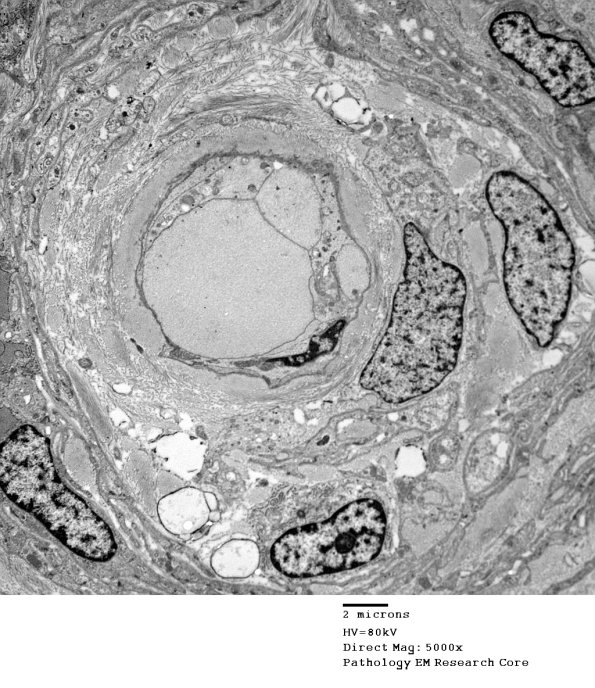

The central structure consists of Schwann cells and collagen. (electron micrograph)